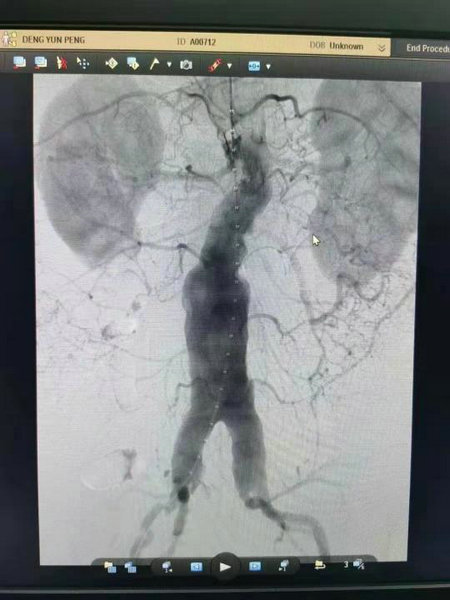

术中造影显示腹主动脉及双侧髂动脉瘤

覆膜支架主体置入 支架置入后造影无内漏